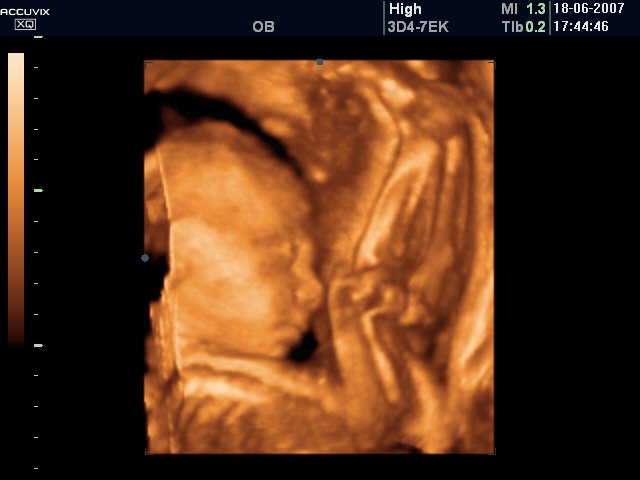

Малко се разочаровах само, че апарата не беше 4Д и нямаме клипче, а пак само снимки, но нищо...нали и мойта лекарка ще си има скоро, пък и важното е, че всичко с бебка е наред, като се роди бебка ще си я гледаме 4 Д постоянно